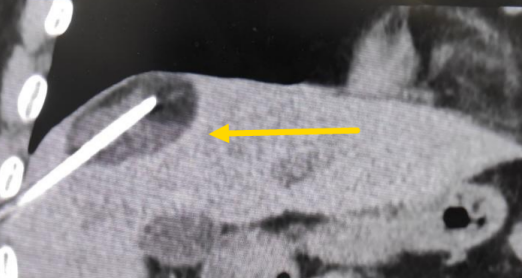

這個(gè)患者病變位置刁鉆,穿刺難度大,冷凍消融的難點(diǎn)在于既要不損傷膈肌和肺組織,同時(shí)又要盡最大可能完全消融腫瘤。術(shù)前陳寶瑩主任、李鐵柱教授、兀云飛醫(yī)生詳細(xì)設(shè)計(jì)進(jìn)針路徑、布針計(jì)劃,術(shù)中微創(chuàng)團(tuán)隊(duì)協(xié)調(diào)配合,李鐵柱教授仔細(xì)操作,精準(zhǔn)到位,順利完成兩個(gè)病變的布針,遂啟動治療,先快速降溫到-150多度,再升溫至15?,經(jīng)過兩個(gè)循環(huán)反復(fù),即刻觀察到病變完全被冰球覆蓋,同時(shí)周圍臟器無損傷,術(shù)中患者幾乎沒有疼痛,還和醫(yī)生聊起了天。

術(shù)中冰球形成